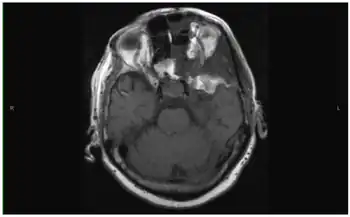

Large 4.4 cm × 4 cm × 3.4 cm mass in the left cavernous sinus extending into the left optic nerve and optic chiasm

Brain tumor can be visualized very well on CT scan, but MRI gives better detail and is the preferred study. Clinical localization of brain tumors may be possible by virtue of specific neurologic deficits or symptom patterns. Tumor at the base of the frontal lobe produces inappropriate behavior, optic nerve atrophy on the side of the tumor, papilledema on the other side, and anosmia.